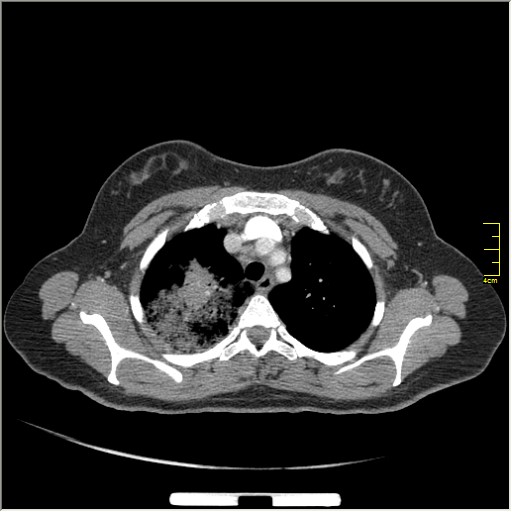

Далее рекомендуем лабораторные исследования, КТ легких.

KT

Давайте определимся, для начала обозначим какие КТ признаки мы видим на представленных сканах. И главное это не перечисление вариантов диагнозов (если нет однозначного варианта); а определить что надо сделать следующим этапом для достижения окончательного диагноза.

ИМХО на следующем этапе-КТ контроль в динамике на фоне лечения(антибиотикотерапии)

Вполне адекватная тактика. КТ контроль через 3-4 недели после антибактериальной терапии, совершенно правильно.

В данном случае, пульмонолог решил пойти на бронхоскопию; был забор материала. Лабараторный анализ (ПЦР) выявил положительную реакцию на туберкулёз.